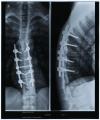

Уважаемые форумчане, первый раз открываю тему на форуме, очень надеюсь что кто-то откликнется. Молодой парень (1983 года рождения) Бабаев Зохраб попал в тяжелую аварию в октябре 2009г. Ему сделали операцию, но, к сожалению, как позже выяснилось, неудачно. Он не ходит и даже не чувствует ног.

Зохраб послал рентген и анамнез врачу. Вот ответ врача:

стоимость лечения (обследование, операция, послеоперационная реабилитация) составит 3.500 - $. Постараемся оставить ваш имплантат (сообщите какой стоит чтобы мы могли подготовиться). Прогноз на то чтобы встать будет известен после ревизии спинного мозга и в ближайшем послеоперационном периоде.

Деформацию позвоночного столба мы постараемся исправить, станет понятно после вашего обследования.